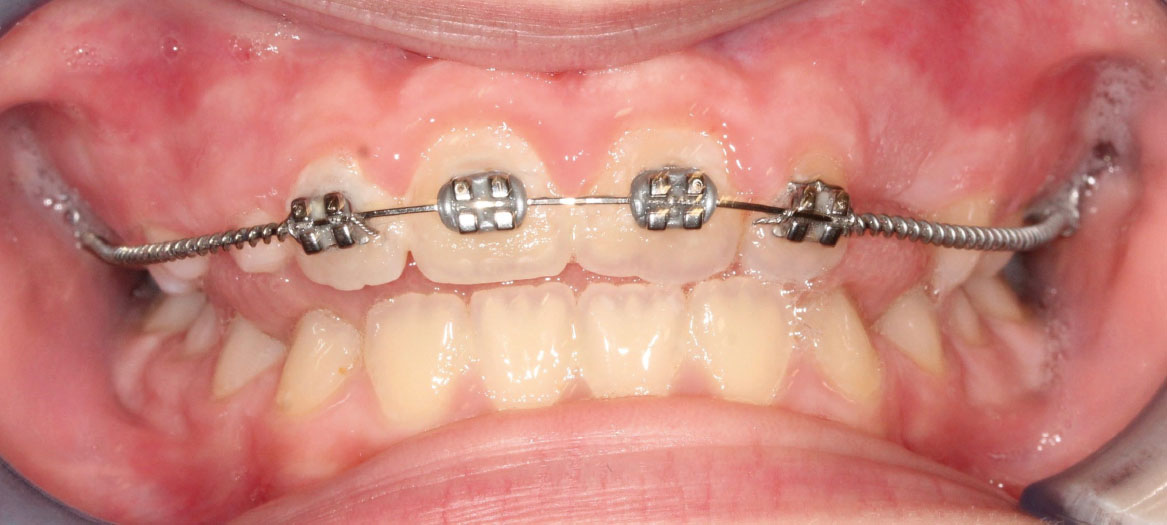

L’overjet e l’overbite sono entrambi ridotti in massima intercuspidazione. Trasversalmente il mascellare superiore è contratto (fig. 4-7).

Fig. 4A Foto intraorale in massima intercuspidazione.

Fig. 4B Foto intraorale in massima intercuspidazione.

Fig. 4C Foto intraorale in massima intercuspidazione.